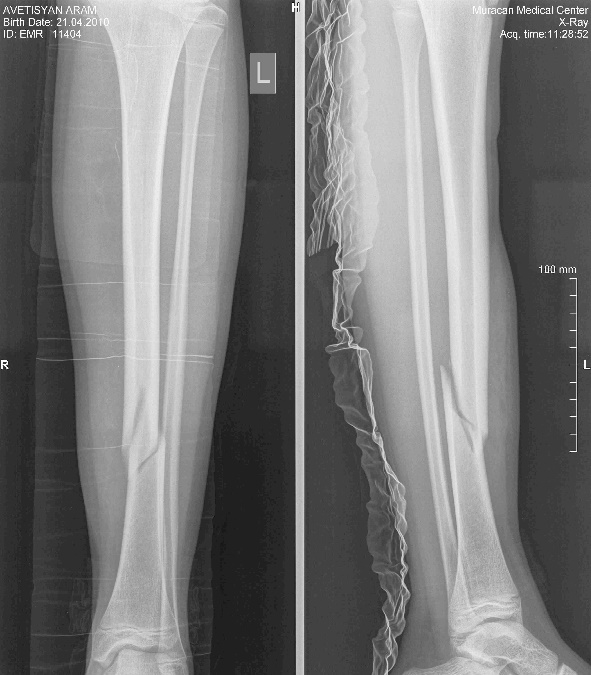

Այս ուսումնասիրությունը հիմնված է 21 հիվանդների (17 տղա, 4 աղջիկ) շարունակական խմբի բուժման արդյունքների վերլուծության վրա, որոնք ենթարկվել են տիտանե էլաստիկ մեխերով վիրահատության։ Հիվանդների տարիքը եղել է 4 տարեկանից մինչև 16 տարեկան։ 9 երեխայի մոտ կոտրվածքի պատճառ է հանդիսացել ձեռքի վրա անկումը, մնացածի մոտ կոտրվածքն առաջացել է վերջույթի ոլորման արդյունքում, վնասվածքի մեխանիզմը եղել է ուղիղ: 19 դեպքերում կոտրվածքները եղել են փակ, իսկ 2 դեպքում՝ բաց։ Ըստ վնասվածքի տեղայնացման՝ դրանք եղել են դիաֆիզար կոտրվածքներ (15 դեպք), պրոքսիմալ մետաֆիզի մակարդակի կոտրվածք (3 դեպք) և հեռավոր մետաֆիզի՝ (3 դեպք): Կոտրվածքային գծի բնույթի համաձայն՝ դիաֆիզային կոտրվածքներից հայտնաբերվել են 6 լայնակի, 4 թեք, 5 պտուտակաձև։ Մի տղայի մոտ (4 տարեկան), որի մոտ առկա էր սրունքի մ/3-ի բաց թեք կոտրվածք տեղաշարժով և մաշկի մինուս հյուսվածքներով, կատարվել է նաև վերքերի առաջնային վիրաբուժական մշակում և կարում՝ ռետինյա արտաթորիչներով։ Սակայն մի քանի շաբաթ անց սկսվել է մաշկի նեկրոզ։ Այդ իսկ կապակցությամբ կատարվել է երկրորդ վիրահատական միջամտությունը։ Կատարվել է մաշկի աուտոտրանսպլանտացիա։ Մաշկի կտորները վերցվել են առողջ ազդրի առաջային մակերեսից: (Նկ 1)